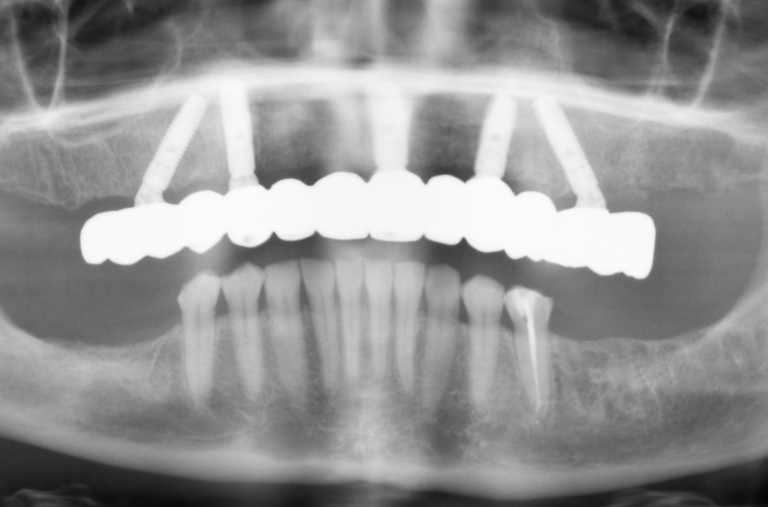

You will first undergo a thorough evaluation to determine if dental implants are the best solution for your dental issues. This includes a comprehensive examination and a 3D scan (cone-beam CT scan) to assess your jawbone’s density and the most strategic location/s for the implant/s. If there is insufficient bone, a bone graft may be recommended to reinforce the area and ensure the implant’s long-term success.

Implant Placement

During the surgical procedure, the following steps are performed:

- Local anesthesia is administered to ensure comfort during the procedure.

- A small incision is made in the gum tissue to access the jawbone.

- A hole is carefully drilled into the bone to place the implant.

- The implant is inserted into the hole, and the gum tissue is stitched up.

Following the surgery, the implant undergoes a process called osseointegration, wherein it is fused with the bone as the latter heals over a period of three to six months. Some patients may have a temporary tooth or other prosthetic attached during the same appointment, while others may require multiple visits to ensure optimal healing and placement.